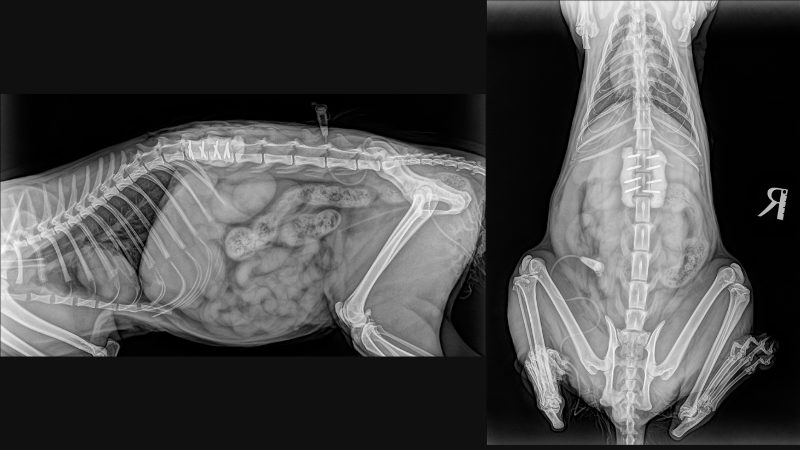

<手術後のレントゲン>

ピンと医療用セメントで固定しました。